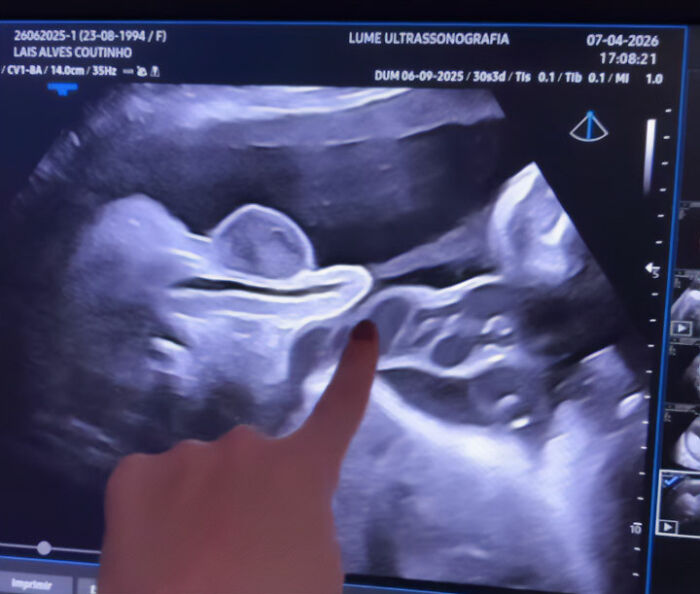

This month, a pregnant doctor named Lais Coutinho sparked curiosity by sharing an ultrasound that captured the exact moment her son peed inside the womb.

A doctor went viral after showing an ultrasound of her fetus urinating in the womb

The video has amassed millions of views, igniting interest in how bodily functions work before birth.

Image credits: dralaiscoutinho